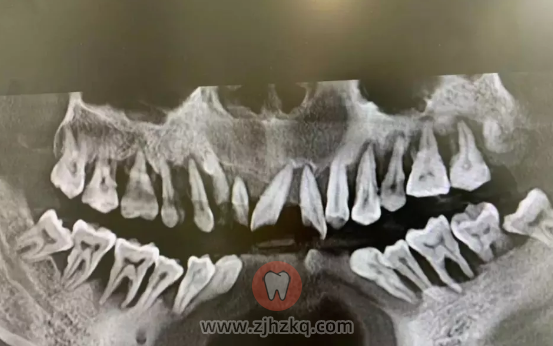

牙周炎是由牙菌斑生物膜引起的牙周组织的慢性感染性疾病,本病的发生与牙菌斑、宿主全身易感因素有关。牙周炎会引起牙龈、牙周膜、牙槽骨和牙骨质炎症,导致牙周袋形成、牙槽骨吸收甚至牙齿松动丧失,是我国成人丧失牙齿的首位原因。

牙周炎长期不治疗可能使牙组织逐渐遭到破坏,牙槽骨损害,牙齿松动,最终导致牙齿脱落。由于牙齿无力咀嚼食物,可引起消化不良、营养缺乏,从而导致消化道的溃疡性疾病。

在生活中有70%的人都会因为不良口腔习惯、不良生活喜好引发不同程度的牙周炎,如果牙周炎太严重就需要拔牙治疗。而成年人的牙齿不可以再长出来,一旦拔牙就要尽快治疗,否则缺牙过久会导致牙齿位移、面容衰老等严重后果。